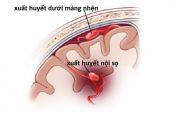

Bệnh xuất huyết dưới nhện là sự chảy máu đột ngột vào khoang trống ở giữa não và lớp màng bao phủ não. Tình trạng này rất nguy hiểm nếu không được điều trị. Bài viết dưới đây sẽ nói rõ hơn về triệu chứng, nguyên nhân và cách điều trị của bệnh, mời các bạn tham khảo!